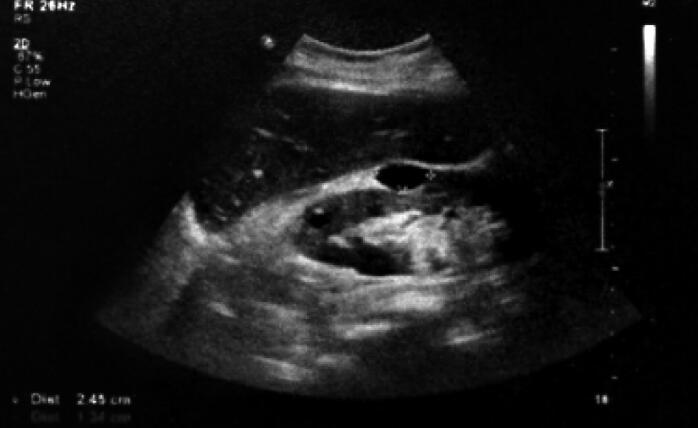

心脏超声:主动脉瓣置换术后,未见明确异常(图1)。

图1  入院超声心动图结果

主动脉瓣为人工瓣,瓣架固定,瓣叶启闭灵活,瓣周未见异常回声附着,余各瓣膜形态结构未见异常,主动脉瓣向前血流速度最大约为3.9m/s,最大压差约为62mmHg